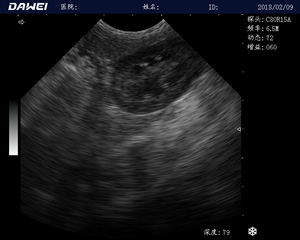

MT15獸用B超機適用探頭

牛羊馬豬犬貓及多種家禽、實驗動物、野生動物、及部分水生動物

中小動物的肝、膽,脾、腎、膀胱、子宮、妊娠等各組織器官的檢查和病變的診斷